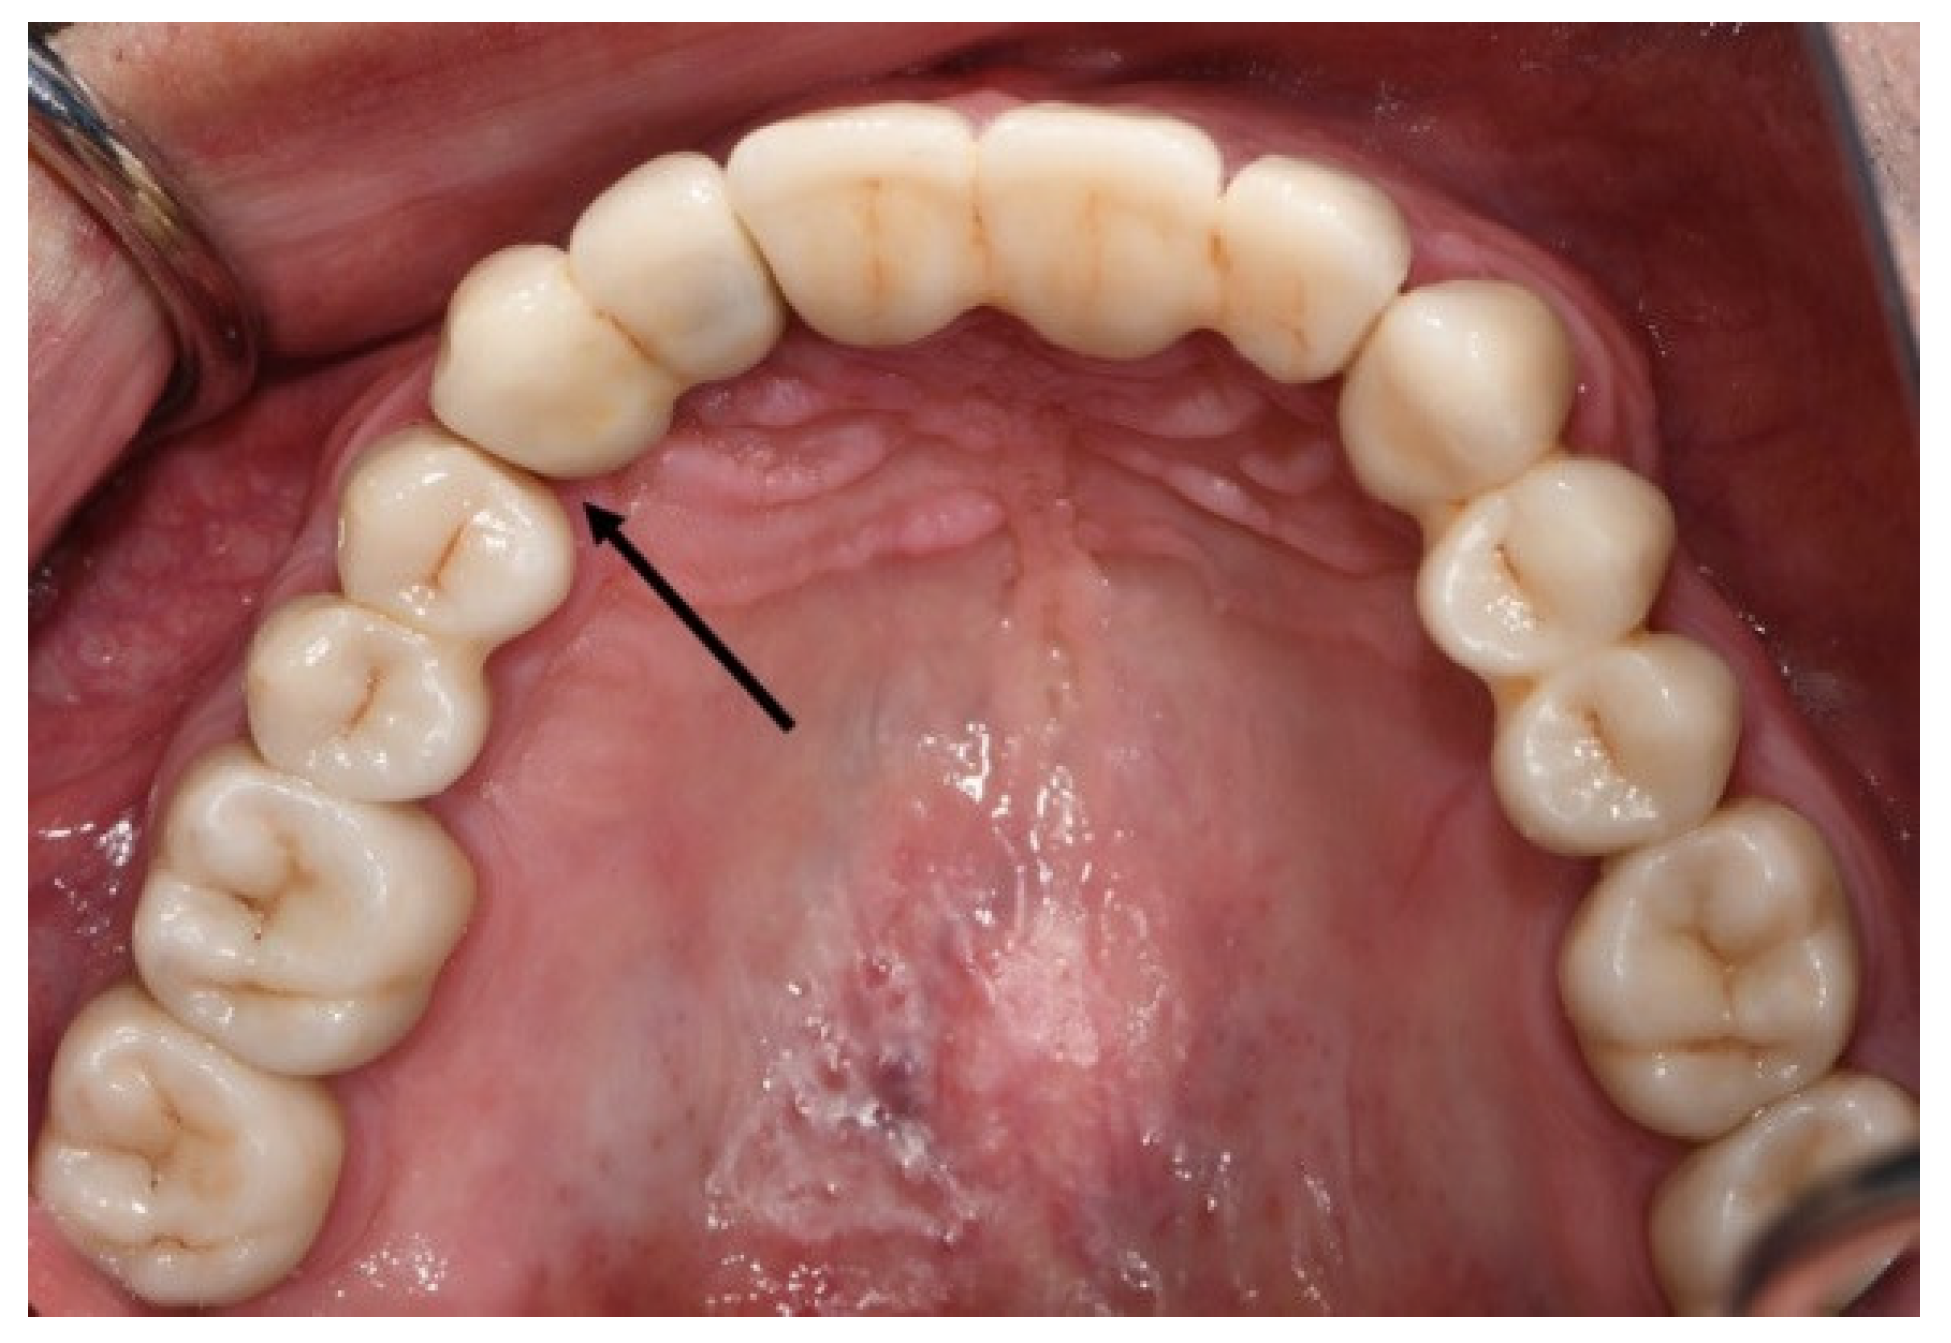

2.4. Methods

2.5. Clinical and Radiographic Assessments and Classification of Observed Events at the Recall Appointment